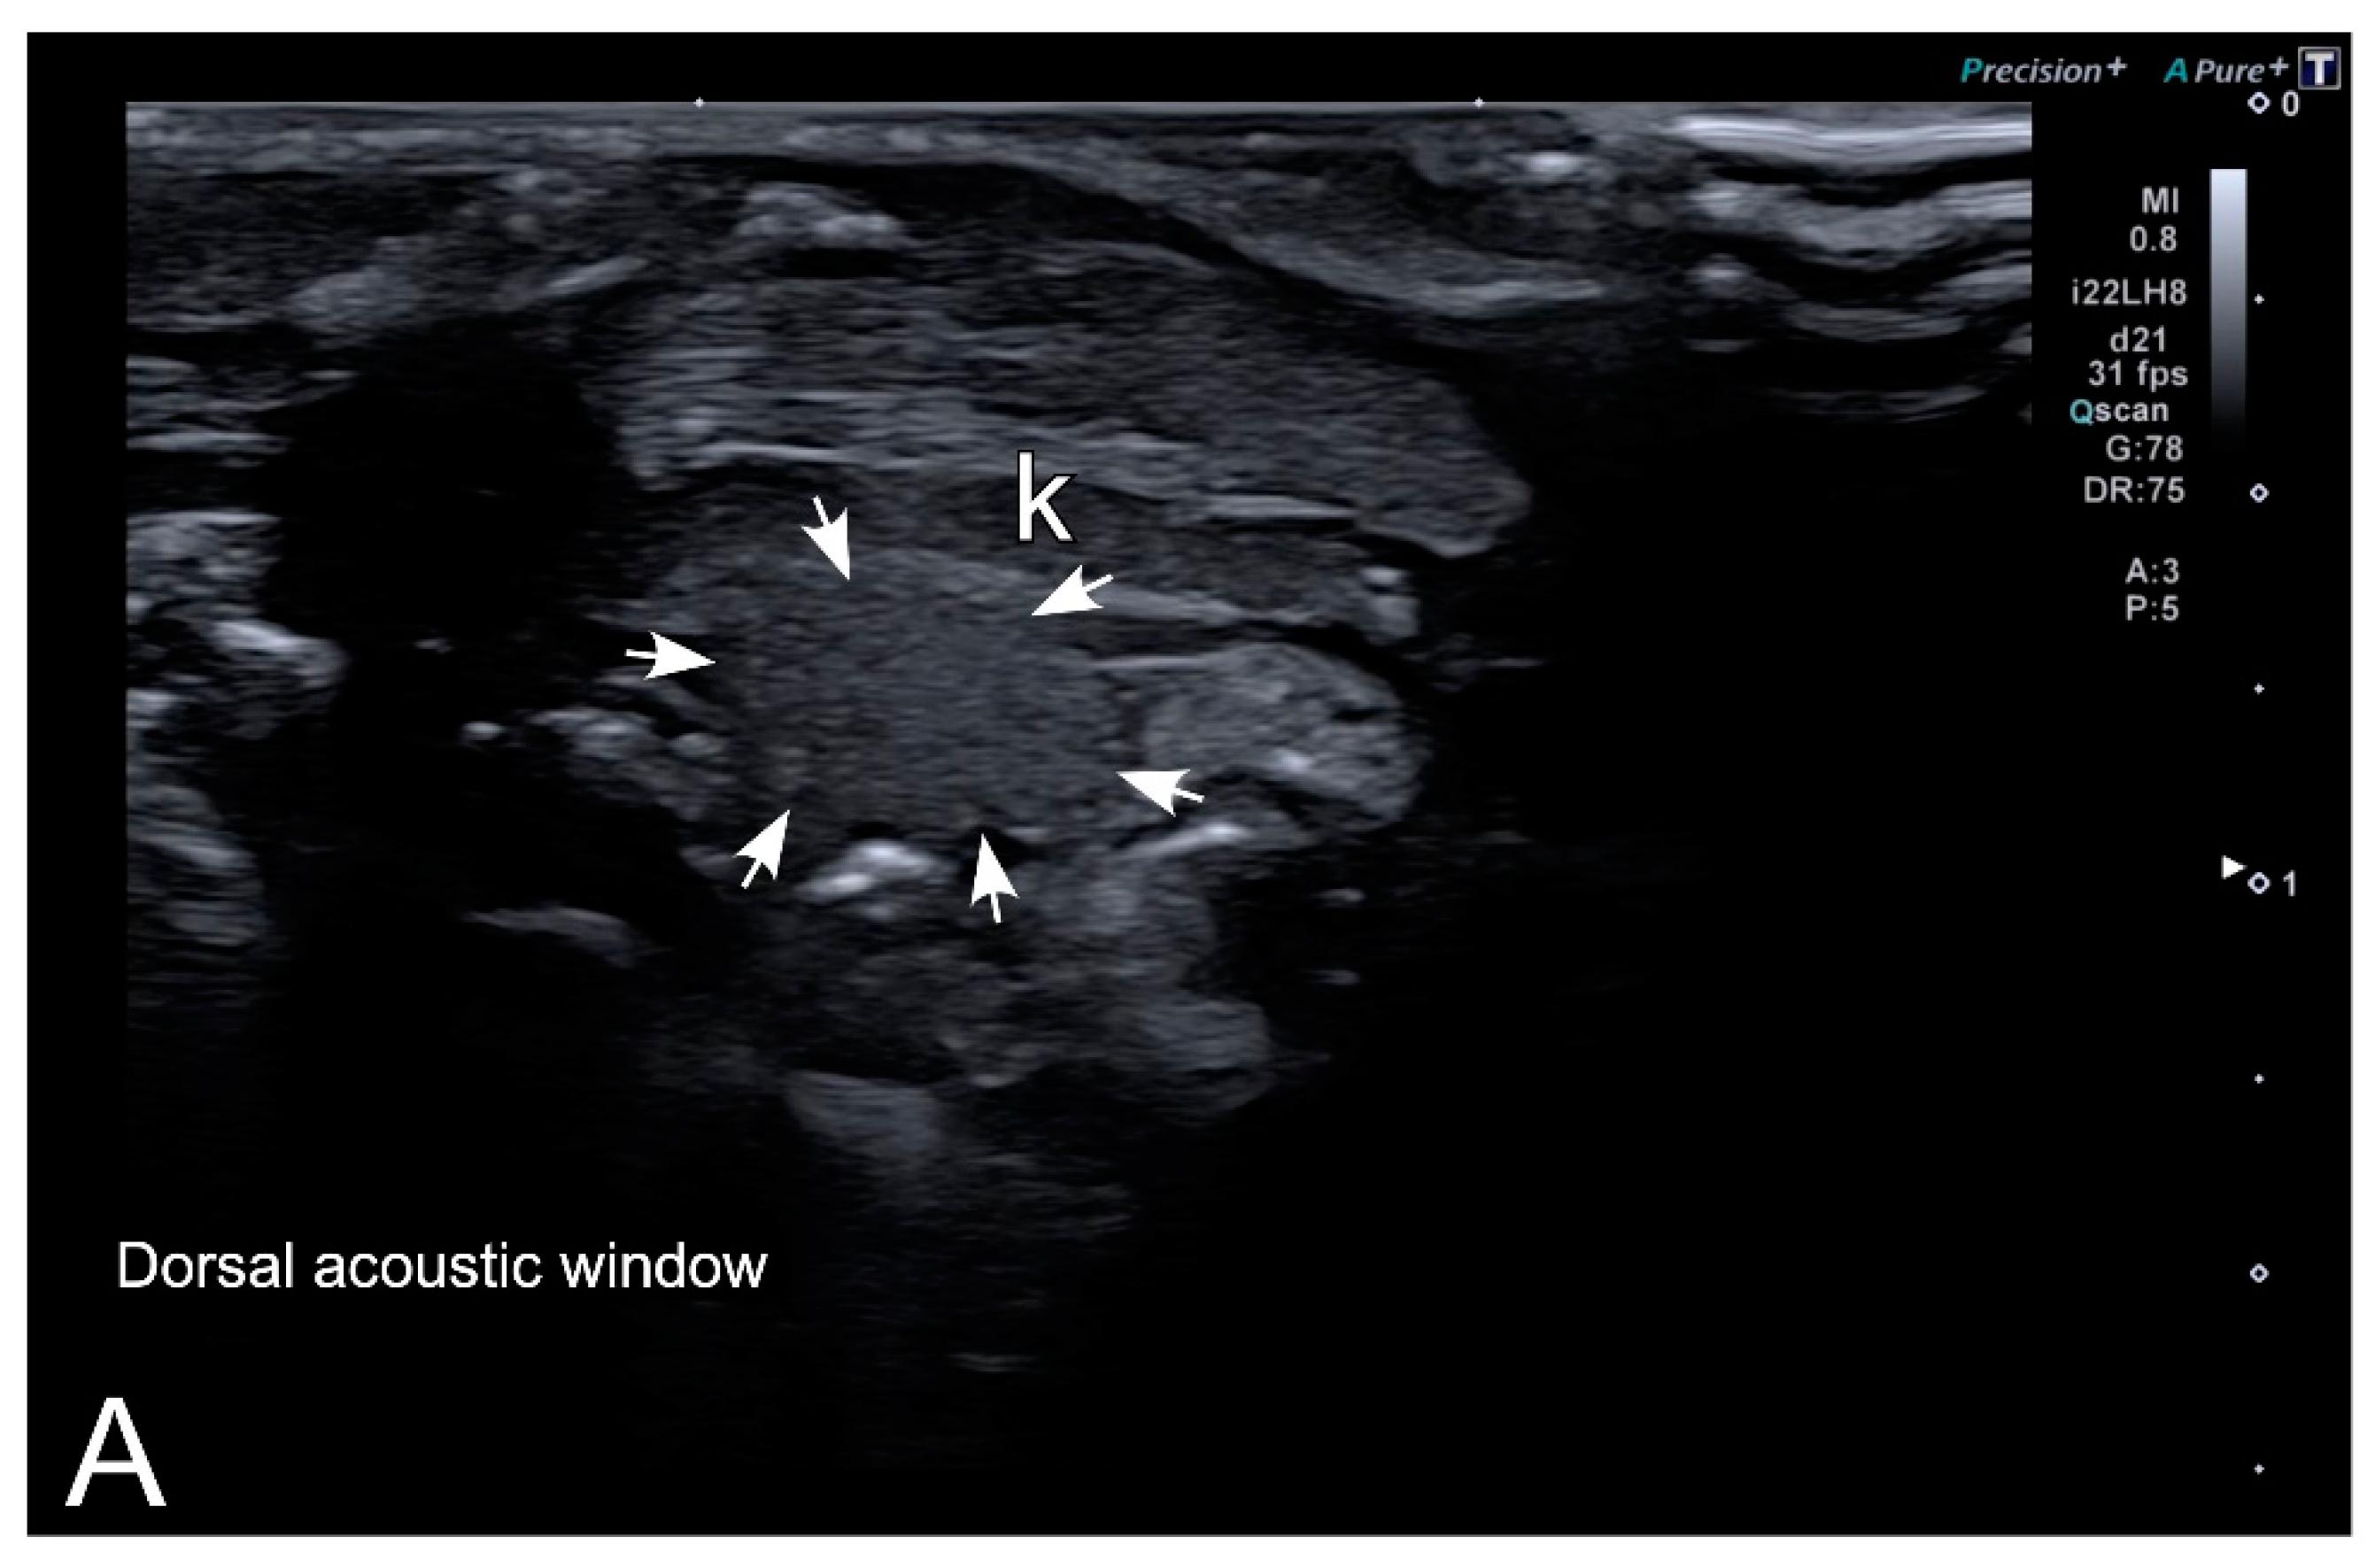

Figure 7. Representative HR-US images of Kaloula pulchra (A) and Xenopus laevis (B) males obtained in the longitudinal plane using a dorsal acoustic window. The testes (delimited by arrows) appeared as structures with oval morphology, mid echogenicity and homogenous echotexture. Testes were located just ventral or ventrolateral of the ipsilateral kidney (k).